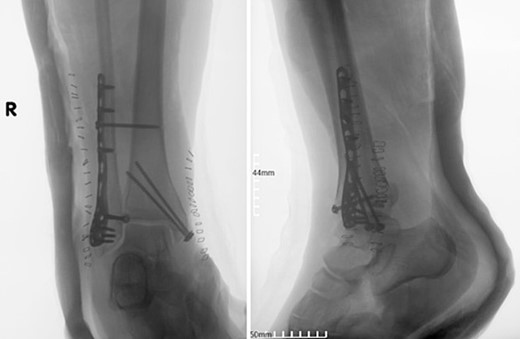

Four doses of i.v. cefoxitin (2000 mg 5 minutes prior to skin incision in the operating room and 1000 mg three times postoperatively every 8 h) were administrated as chemoprophylaxis. The postoperative period was well-progressed, and the patient was discharged on the second postoperative day with a cast and instructions against weight-bearing. In the seventh postoperative week, the patient deviated from the prescribed postoperative regimen by prematurely initiating weight-bearing activities, contrary to the surgeon’s explicit recommendations. During the regular 8-week follow-up, we observed after the radiological evaluation that the syndesmotic screw was broken. This necessitated us to remove the screw and replace it with a 3.5-mm cortical screw (Fig. 3).

Anteroposterior and lateral X-ray of the ankle joint showing the broken syndesmotic screw and the replacement with a 3.5-mm cortical screw on the lateral malleolus 8 weeks after the initial surgery.